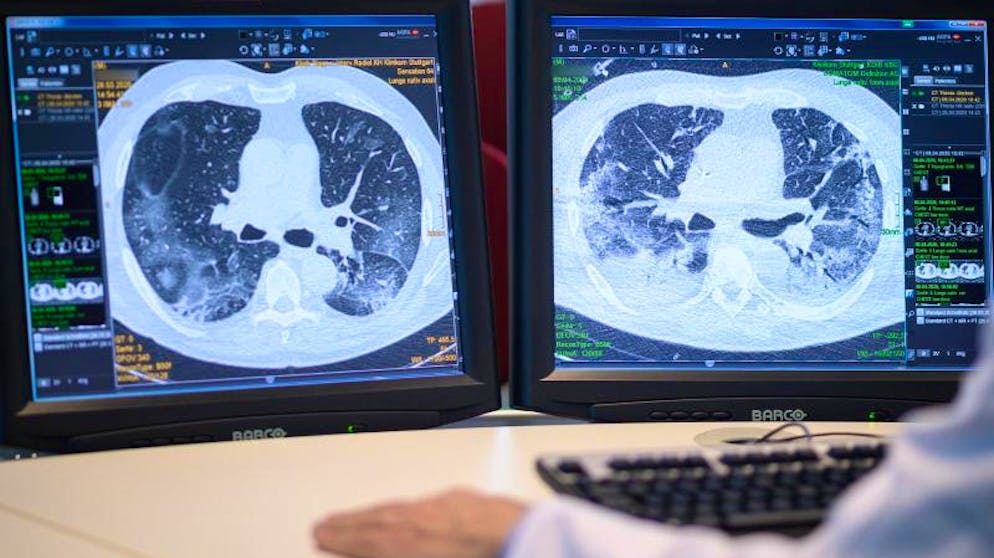

Auf zwei Monitoren sind am Klinikum Stuttgart Computertomographieaufnahmen der Lunge eines Covid-19-Patienten zu sehen. Foto: Sebastian Gollnow/dpa